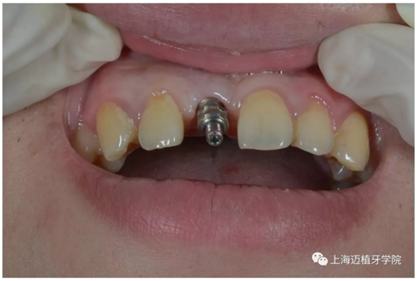

口內(nèi)個性化基臺:

戴牙 最終修復效果